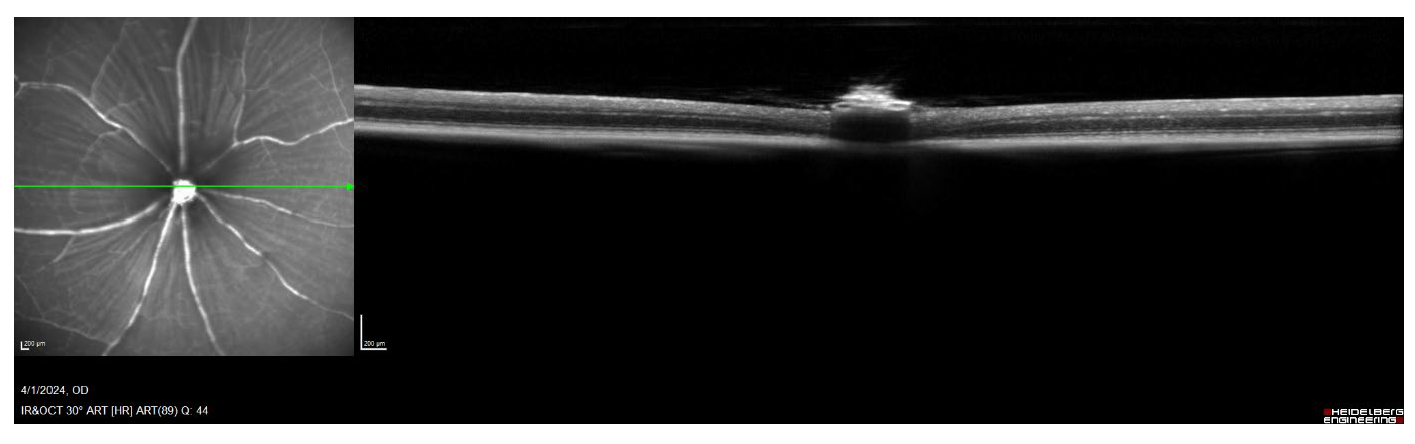

Figure 8. OCT imaging allows for longitudinal cross-section scans of the retina to be collected. These scans allow for the measurement of retinal thickness, which sheds light on changes in the ganglion cell layer following optic nerve crush.